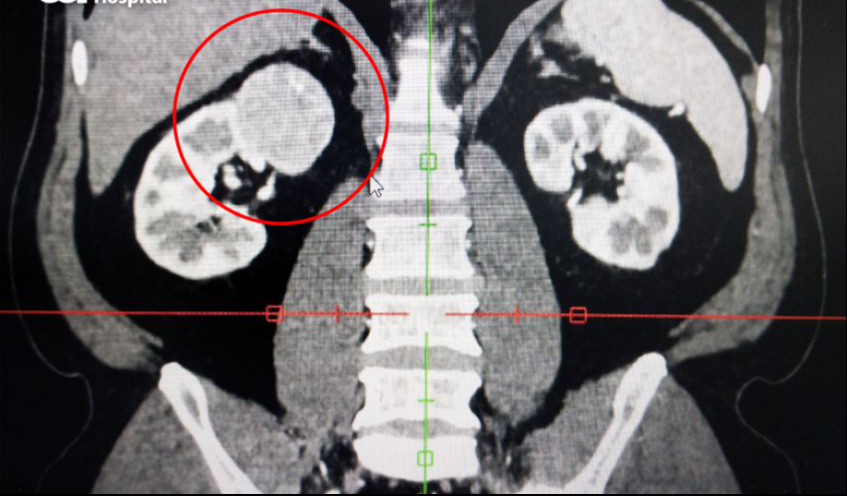

Theo thông tin từ BVĐK Tâm Anh, Ths, Bs Nguyễn Tân Cương, Phó khoa Tiết niệu, Trung tâm Tiết niệu – Thận học – Nam khoa cho biết, qua ảnh chụp cắt lớp vi tính (CT-scanner) nhận thấy khối u thận phải có kích thước 4,5×5,0 cm, ở cực trên thận phải, đậm độ không đồng nhất, u nằm sát tĩnh mạch thận phải (mạch máu đưa máu từ thận về tim), gần tĩnh mạch chủ bụng, ngay bên dưới gan, gần tá tràng (phần ruột non nối với dạ dày) và đại tràng.